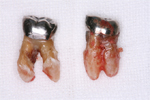

銀歯の2本は残せないと判断

抜歯した歯

抜歯した歯